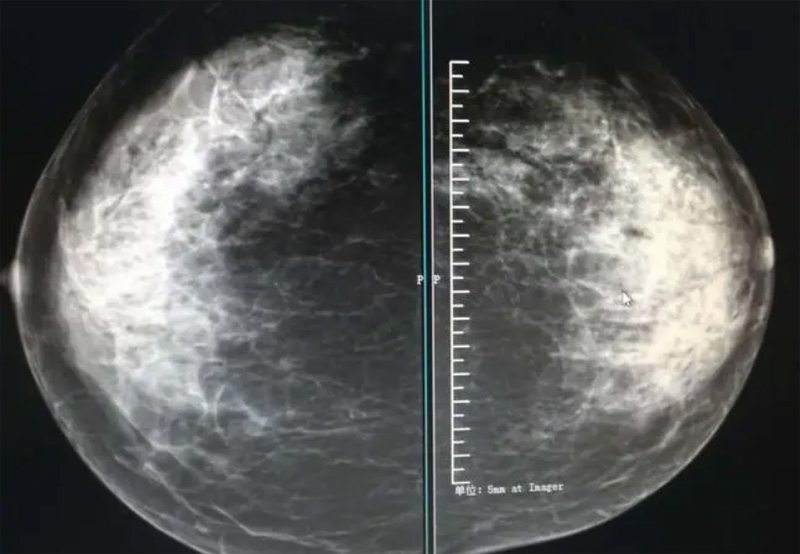

攝影診斷規(guī)范乳腺DR有頭尾位及內(nèi)外側(cè)斜位診斷概念和診斷術(shù)語

乳腺DR的檢查中為了讓乳腺相關(guān)疾病的篩查需要更高質(zhì)量的檢查圖像。檢查前期的準(zhǔn)備工作非常重要。醫(yī)生跟病患的有效溝通。要跟檢查者說明檢查過程,特別是體位跟擠壓乳房帶來的不適應(yīng)。放松心情,檢查過程中得到充分的合作。正確的擺正位置乳腺DR可以拍攝到更優(yōu)質(zhì)清洗高質(zhì)量的X線圖像。乳腺DR檢查需要再月經(jīng)后檢查,但是對病癥明顯的就不受這個限制。

乳腺DR攝影體位有頭尾位及內(nèi)外側(cè)斜位,

乳房在片子的中央,乳頭切線位,可見小部分胸大肌,內(nèi)側(cè)乳腺組織應(yīng)全部包括在片中,外側(cè)乳腺組織盡可能包括在片中。一張好的MLO位圖像顯示如下:乳房被推向前上,乳腺實質(zhì)充分展開,胸大肌可見,較松弛,下緣達(dá)到乳頭水平,乳頭在切線位,部分腹壁包括在片中,但與下部乳腺分開,絕大部分乳腺實質(zhì)顯示在片中。乳腺組織外緣可見乳頭的輪廓;乳腺后方的脂肪組織被很好地顯示出來,乳房無皺褶。對于CC位及MLO位顯示不良或未包全的乳腺實質(zhì),可以根據(jù)病灶位置的不同選擇以下體位:外內(nèi)側(cè)位(LM)、內(nèi)外側(cè)位(ML)、內(nèi)側(cè)頭尾軸位(MCC)、外側(cè)頭尾軸位(LCC),尾葉位(CLEO)及乳溝位。在臨床實踐中,對于常規(guī)體位上發(fā)現(xiàn)的異常改變,可以進(jìn)一步采取一些特殊的攝影技術(shù),包括局部加壓攝影、放大攝影或局部加壓放大攝影技術(shù)。

3、乳腺實質(zhì)背景的確定:觀察乳腺實質(zhì)與脂肪的構(gòu)成比例,了解乳腺實質(zhì)類型,以判斷對某些乳腺攝影征象敏感性的影響,有利于確定乳腺攝影對疾病的診斷價值。

必須指出的是,美國放射學(xué)會提出的乳腺影像報告和數(shù)據(jù)系統(tǒng)(Breast Imaging Reporting and Data System, BI-RADS)將乳腺分為4型:脂肪型(乳腺內(nèi)幾乎全部為脂肪組織,腺體組織占25%以下)、少量腺體型(乳腺內(nèi)散在腺體組織,大約占25%~50%)、多量腺體型(乳腺呈不均勻致密表現(xiàn),腺體組織大約占51%~75%)、致密型(乳腺組織非常致密,腺體組織占75%以上)。這種分型的主要意義在于說明X線對不同乳腺類型中病變檢出的敏感性不同,對發(fā)生在脂肪型乳腺中病變的檢出率很高,而對發(fā)生在致密型乳腺中病變的檢出率則有所降低,臨床醫(yī)師了解這一點很重要。